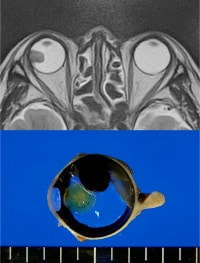

●ぶどう膜悪性黒色腫(眼内メラノーマ)

IgG4関連疾患とは、血清IgG4が上昇し、全身の諸臓器にリンパ形質細胞浸潤病変を呈する疾患概念です。眼科領域ではIgG4関連涙腺炎が代表的な病態です。(図は本疾患のMRI:Takahira et al. Arch Ophthalmol 125:1577-, 2007 から引用)。IgG4陽性病変は涙腺以外の眼窩組織にもみられ、視神経症による視力低下をきたす重症例もあります。またIgG4関連眼疾患ではときにリンパ腫を併発するので、その鑑別診断は重要です。